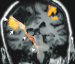

Functional Magnetic Resonance Imaging (fMRI) in Brain Tumour Patients European Association of NeuroOncology Magazine 2012; 2 (3): 123-128 PDF Summary Figures Keywords: brain mapping, brain neoplasms, functional, glioma, magnetic resonance imaging, motor cortex Functional magnetic resonance imaging (fMRI) is increasingly used in the work-up of brain tumour patients preoperatively to assess the relationship between the functionally eloquent cortex and brain pathology. In cases of presumed tumour localisation in or near eloquent brain areas, such as the motor cortex or language areas, fMRI may be advantageous to guide the neurosurgical approach, shorten surgery duration, and obtain prognostic information prior to surgery. For the assessment of the primary motor cortex a good correlation between fMRI and intraoperative electrocortical mapping (ECM) has been reported, with sensitivities and specificities ranging from 88–100 %. For the localisation of language representation areas validation results are controversial with sensitivities from 22–100 % and specificities from 0–100 %, rendering fMRI less suitable as the sole technique for language cortex localisation. For the assessment of hemispheric language lateralisation, however, > 90 % agreement between fMRI and the invasive Wada test has led to fMRI now mostly having replaced the Wada test for this indication. There are several limitations of fMRI including issues that are inherent to the technique such as spatial and geometric uncertainty, tumour effects on the fMRI signal, interand intra-individual variability, lack of discrimination between essential and modulating brain regions, and lack of information on the underlying white matter. Such shortcomings need to explicitly be taken into account in every patient. The careful use of fMRI is justified to aid neurosurgical planning but intraoperative ECM remains the gold standard for localising the eloquent brain cortex. |